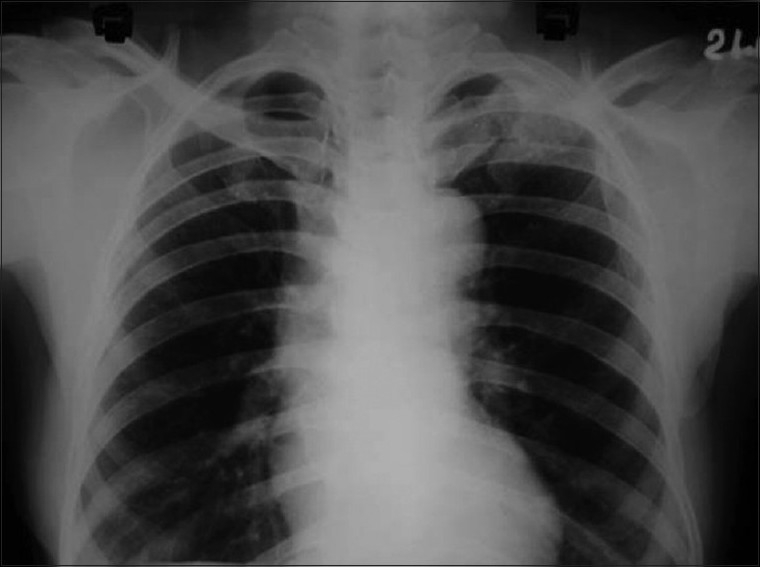

Skiagram of postero-anterior view of the chest revealed a fracture of the left clavicle [Figure 2]. Computerized tomography (CT) scan of the thorax was also advised, but the patient was unable to afford it. X-ray of the left limb showed a circumscribed lytic lesion in the lower shaft of the left femur. A whole-body bone scan (isotopic skeletal survey) with 99 m technetium-methylene diphosphonate revealed abnormally increased uptake over the left clavicle and distal end of left femur [Figure 3]. CT scan of the whole abdomen revealed multiple ill-defined hypodense enhancing space occupying lesions of varying sizes involving both lobes of the liver [Figure 4]. There was a 7.9 × 6.8 cm irregular heterogenous enhancing lesion of the left adrenal gland displacing the upper pole of the left kidney. The adrenal gland of the right side showed no abnormality. There was no retroperitoneal lymphadenopathy. ECG was within normal limits.

| Figure 2 PA view of chest showing fracture of left clavicle